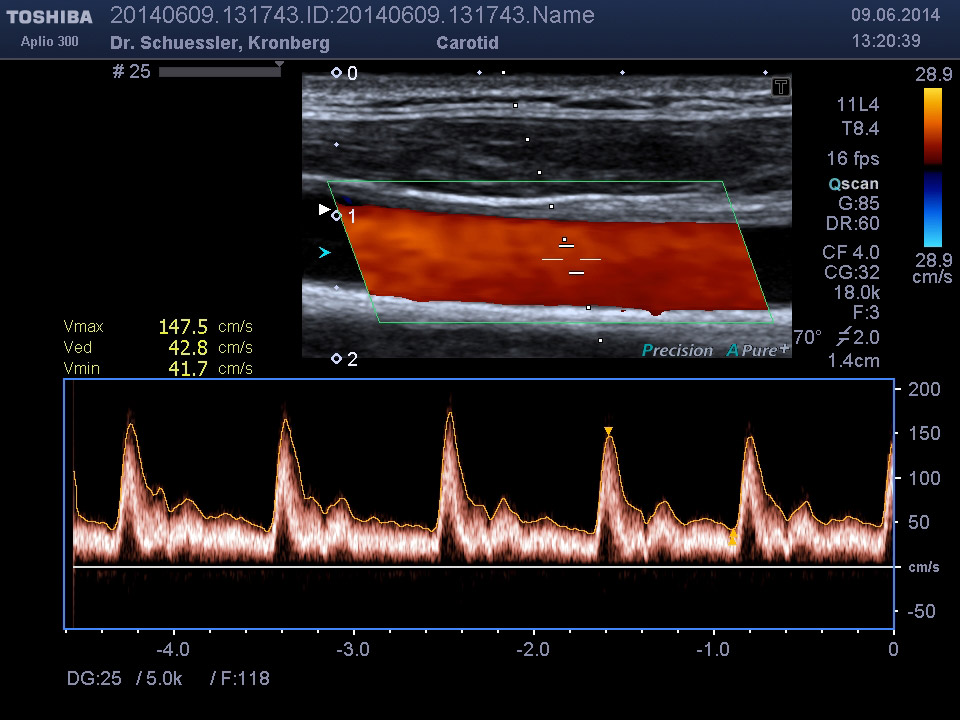

Die farbkodierte Duplexuntersuchung der Gefäße ist ein Ultraschallverfahren und gibt u.a. Auskunft über Verkalkungen, Einengungen, Verschlüsse oder Thrombosen im Bereich der Arterien und Venen.

Die Untersuchung wird angewandt zur Diagnostik von Verengungen in den hirnversorgenden Arterien, Erweiterungen (Aneurysmen) oder Verengungen der Bauchschlagader, Verengungen der Nierenarterien bei Bluthochdruck,  Venenthrombosen und zur Bestimmung des Gefäßrisikoprofils.

Ultraschalluntersuchung der jeweiligen Gefäßregion am liegenden Patienten.